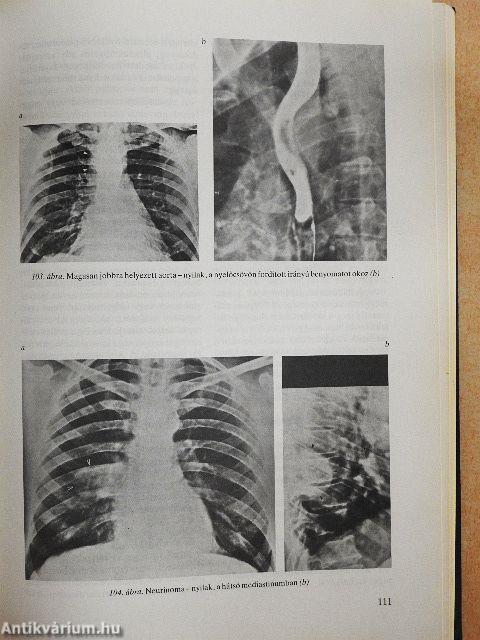

| A mediastinum röntgenvizsgálata | 107 |